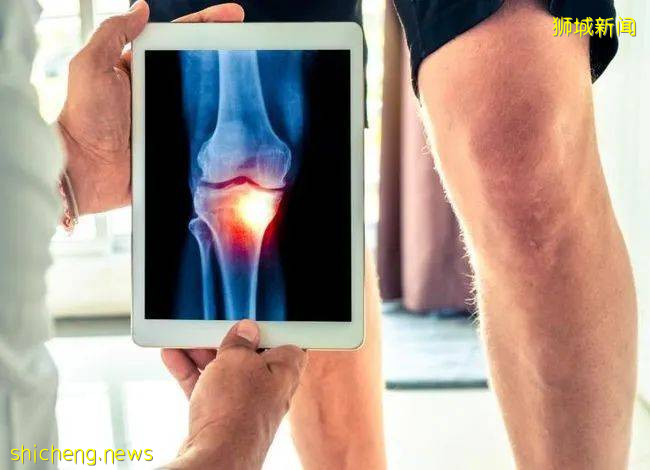

4.关节受损或变形

关节受损和关节变形,是风湿病患者最大的痛。对患者的行动受到极大的限制。而关节变形也会给患者带来非常痛苦的感受。

严重的类风湿关节炎

严重的类风湿关节炎还会导致关节肿胀疼痛,甚至可能丧失活动能力。这病主要是由免疫系统引起,需要通过验血诊断。

类风湿关节炎是导致国人残疾、失去行动能力的疾病之一!

类风湿关节炎和骨关节炎的发病症状表面上相似,但病因不同。它是一种自身免疫病。

免疫系统是人体针对感染病如细菌和病毒的自然防御。患有类风湿关节炎者,免疫系统会制造抗体,和身体的组织起反应,侵袭关节,导致关节持久发热、红肿和疼痛,造成长期慢性炎症。

患者的关节首先有晨僵、疼痛、肿胀症状,影响日常活动,比如走路、手握东西的力量。

之后,患者的关节会在发病初期开始损毁。